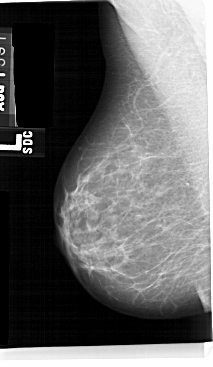

A_1563_1.RIGHT_CC

RIGHT_MLO LINES 5491 PIXELS_PER_LINE 2776 BITS_PER_PIXEL 12 RESOLUTION 43.5 OVERLAY